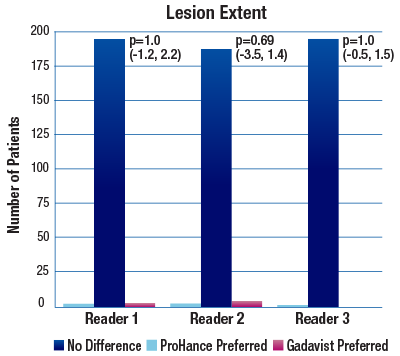

The TRUTH study results demonstrate no differences in contrast enhancement of lesion morphology.1

The 95% confidence intervals for all qualitative assessments confirm that ProHance is not inferior to Gadavist.1

No significant differences noted by any reader for any parameter:1

- Lesion Extent